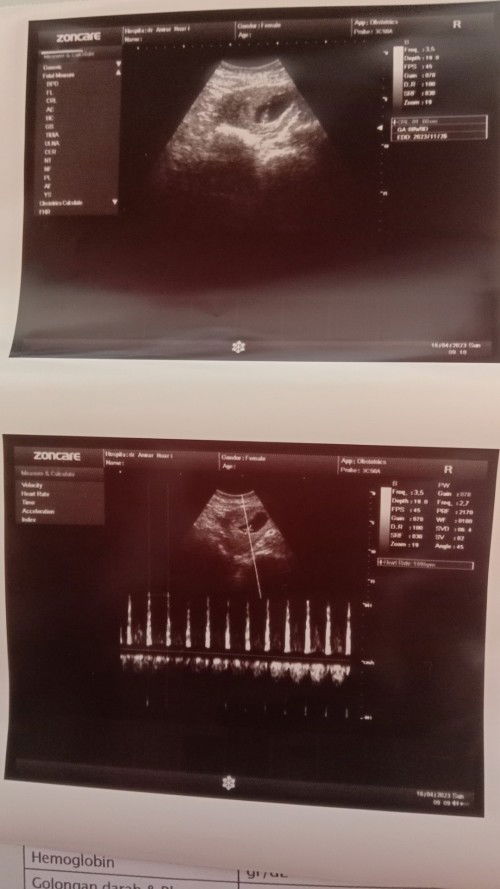

Beda Minggu USG dan hpht

Bun mau tanya dong,aku da kendala nih air ktban rembes dikit2 dh 2 hari yg lalu,klu mnurut hpht 35 mnggu,tp mnurut USG 37 mnggu, Solusi nya Bun hrus di rujuk atau nunggu 1 mngguan LG biar bisa lahir normal atau gmna ya,galau nih..

Alhamdulillah Moms usia 8 week 3 day udh terlihat janin nya dan detak jantung nya udah kenceng bngt..🥰